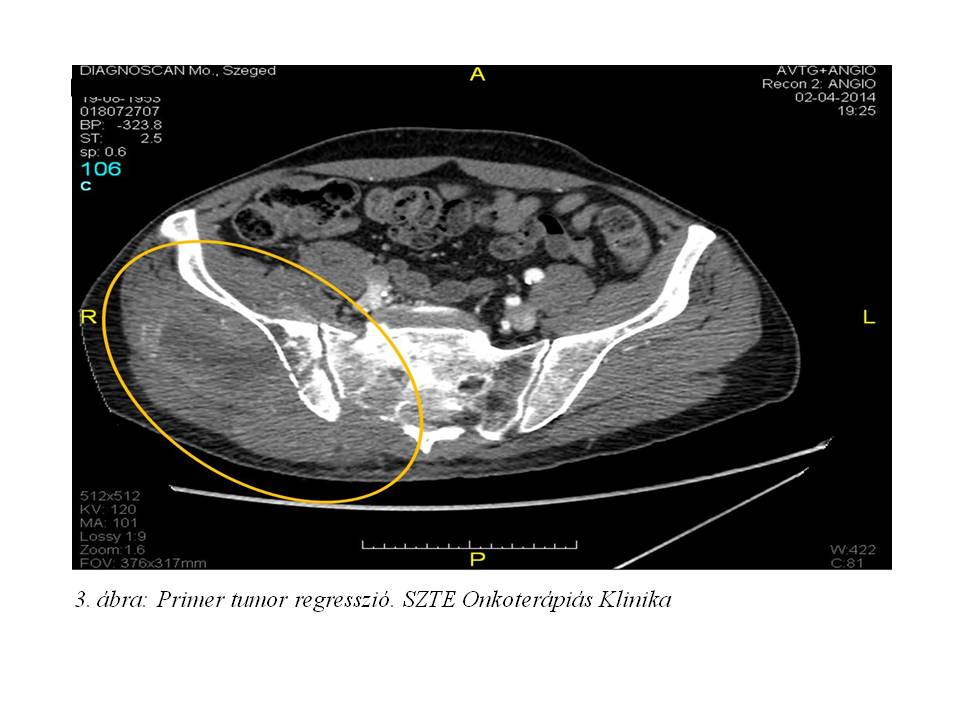

A 3. ciklust követően re-staging has, kismedence, alsó végtagi CT vizsgálat történt (2014.08.11.,3. ábra, 4. ábra), melyen a jobb glutealis régióban leírt térfoglaló folyamat kifejezett regressiót mutatott. A kismedencei propagatio csaknem teljes egészében megszűnt. A jobb arteria iliaca communis szintjétől az arteria femoralis communis oszlásáig az ér továbbra is okkludált, a többi vizsgált artériában lument kitöltő telődés volt megfigyelhető (az occlusio mérséklődött). Ekkor, a korábban a tüdő basisokon leírt metastaticus gócok már nem ábrázolódtak.